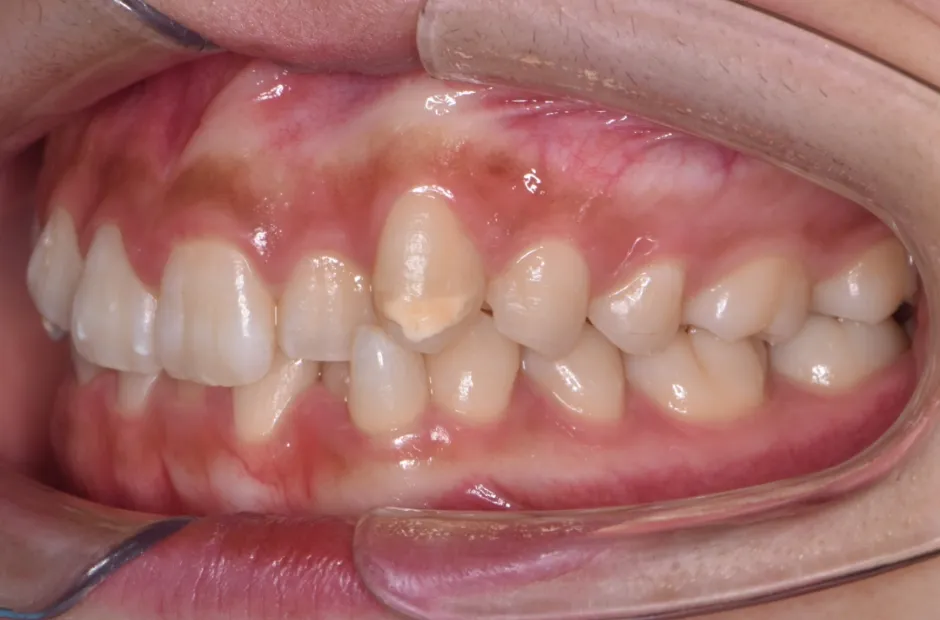

叢生

| 診断名・主訴 | 叢生 |

|---|---|

| 年齢・性別 | 43歳・女性 |

| 治療期間・回数 | 2年7か月 27回 |

| 治療に用いた主な装置 | 舌側矯正 |

| 抜歯部位 | 両顎4,4 |

| 治療費 | 100万円(税抜) |

| リスク・副作用 | 装置による違和感・疼痛・歯肉退縮・歯根吸収・虫歯のリスクなど |